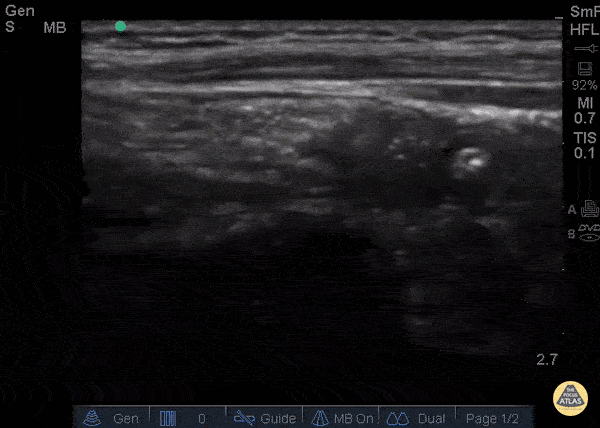

Bowel-GI - Normal Appendix - Cross Section

12 y/o M with nausea vomiting fevers and vague “belly pain.” Patient mildly tender in suprapubic area. POCUS visualized a normal appendix is seen. A normal appendix is identified by a blind-ending tubular structure that is <6mm diameter measured from outer wall to outer wall (although 6mm-7mm has also been described). This patient’s appendix was measure to be 5.1mm (see still image). Dr. Sathya Subramaniam - Children’s Hospital of Philadelphia